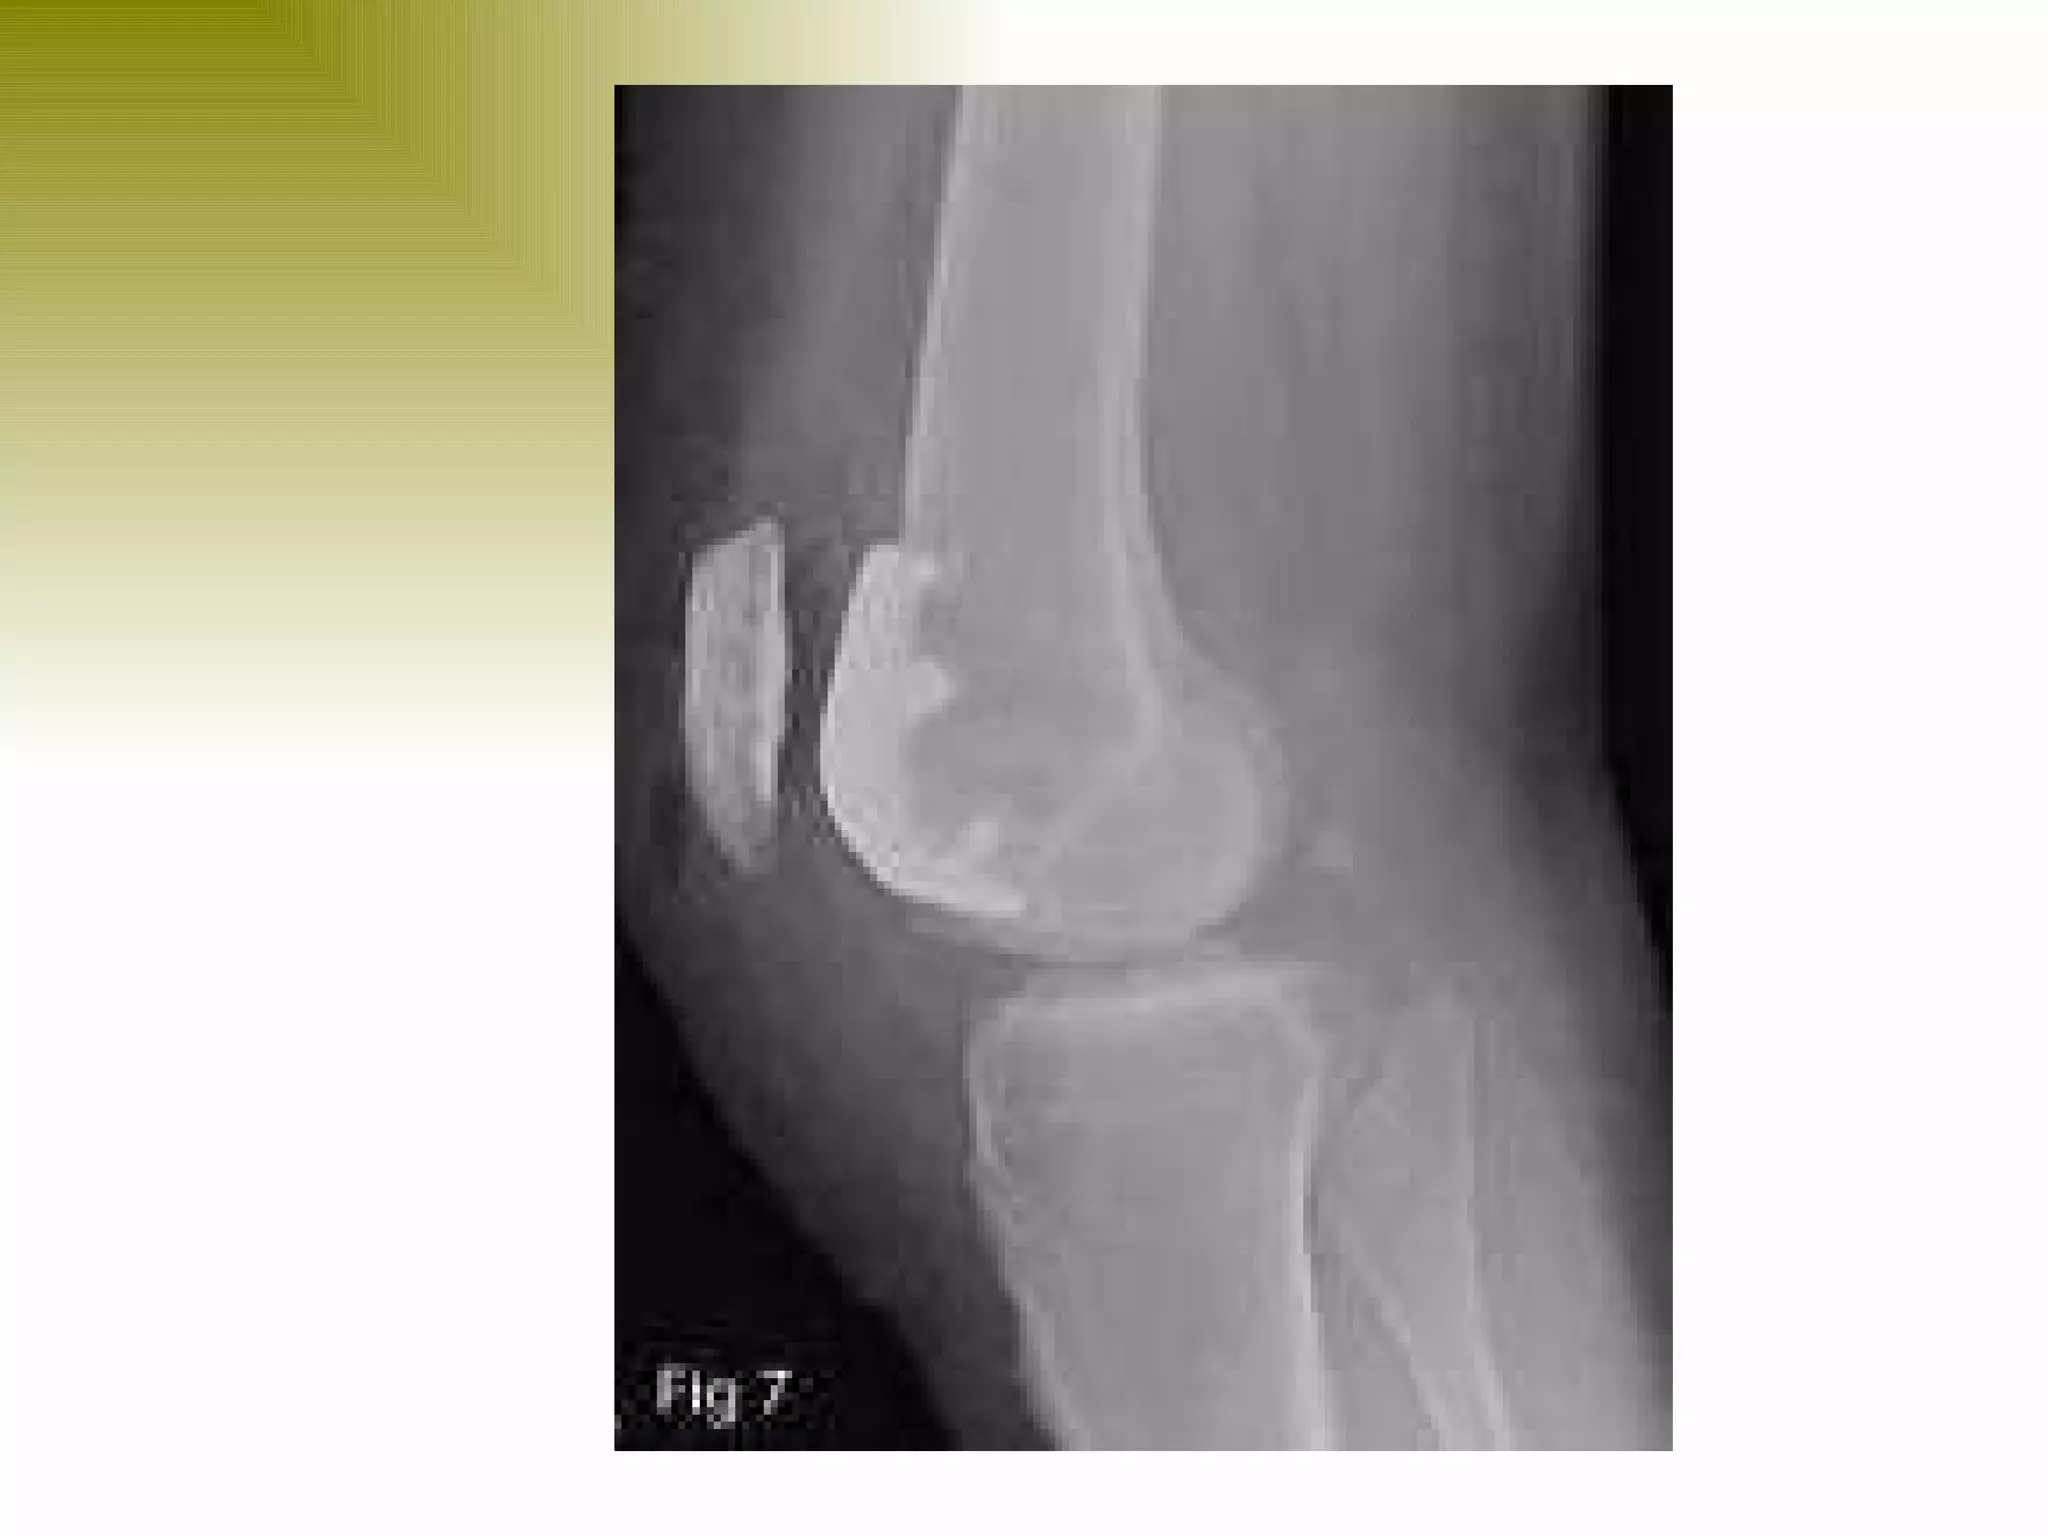

There are three types of patella dislocation: acute, recurrent, and habitual. Acute dislocation occurs suddenly due to quadriceps contraction with the knee flexed and results in the patella dislocating laterally, causing pain, swelling, and inability to straighten the knee. Recurrent dislocations are caused by ligament laxity or anatomical abnormalities and damage bones with repeated dislocations. Habitual dislocations occur every time the knee is flexed and present in early childhood.